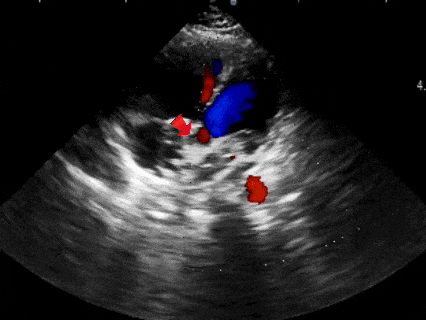

超声下观察封堵器,左右盘面在房间隔两侧,彩超下无残余分流

多普勒观察封堵器成型后无残余分流

多普勒观察无残余分流

释放封堵器

DSA下观察5个Mark点整体移动,封堵器形态良好,封堵成功